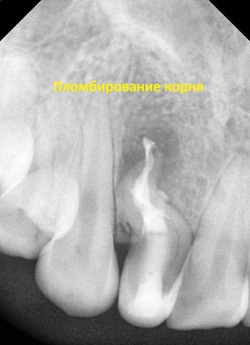

Несмотря на всю сложность клинической ситуации, мы понимали что удаление зуба в столь молодом возрасте несет в себе значительные проблемы для пациентки. В течение 5 визитов нам удалось полность пройти всю сложную анатомию корня данного зуба и провести полноценную очистку и пломбирование.После проведенного лечения у пациентки полностью ушли все болевые ощущения в данном зубе.